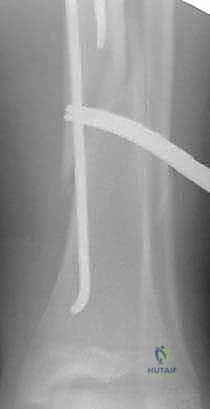

- المسامير النخاعية المرنة (Flexible Intramedullary Nails - TENs): وهي تقنية حديثة ومثالية للأطفال. يتم إدخال مسامير مرنة من التيتانيوم داخل تجويف العظم عبر شقوق صغيرة جداً (Minimally Invasive). تعمل هذه المسامير كدعامة داخلية تسمح للعظم بالالتئام بسرعة دون فتح جراحي كبير، وتوفر ثباتاً ممتازاً.

- تقنية التدخل المحدود (Minimally Invasive): في حالة استخدام المسامير المرنة (TENs)، يتم عمل شقين صغيرين (حوالي 1-2 سم) بالقرب من الركبة أو الكاحل.

- تمرير المسامير والتثبيت: يتم إدخال المسامير المرنة بمهارة فائقة داخل تجويف العظم وتوجيهها لتتجاوز منطقة الكسر، مما يعيد العظم إلى استقامته الطبيعية ويثبته بقوة.

- الإغلاق والتأكد: يتم التأكد من ثبات الكسر وحركة المفاصل المجاورة. تُغلق الشقوق الصغيرة بغرز تجميلية، وتوضع جبيرة خفيفة لحماية الساق في الأيام الأولى.